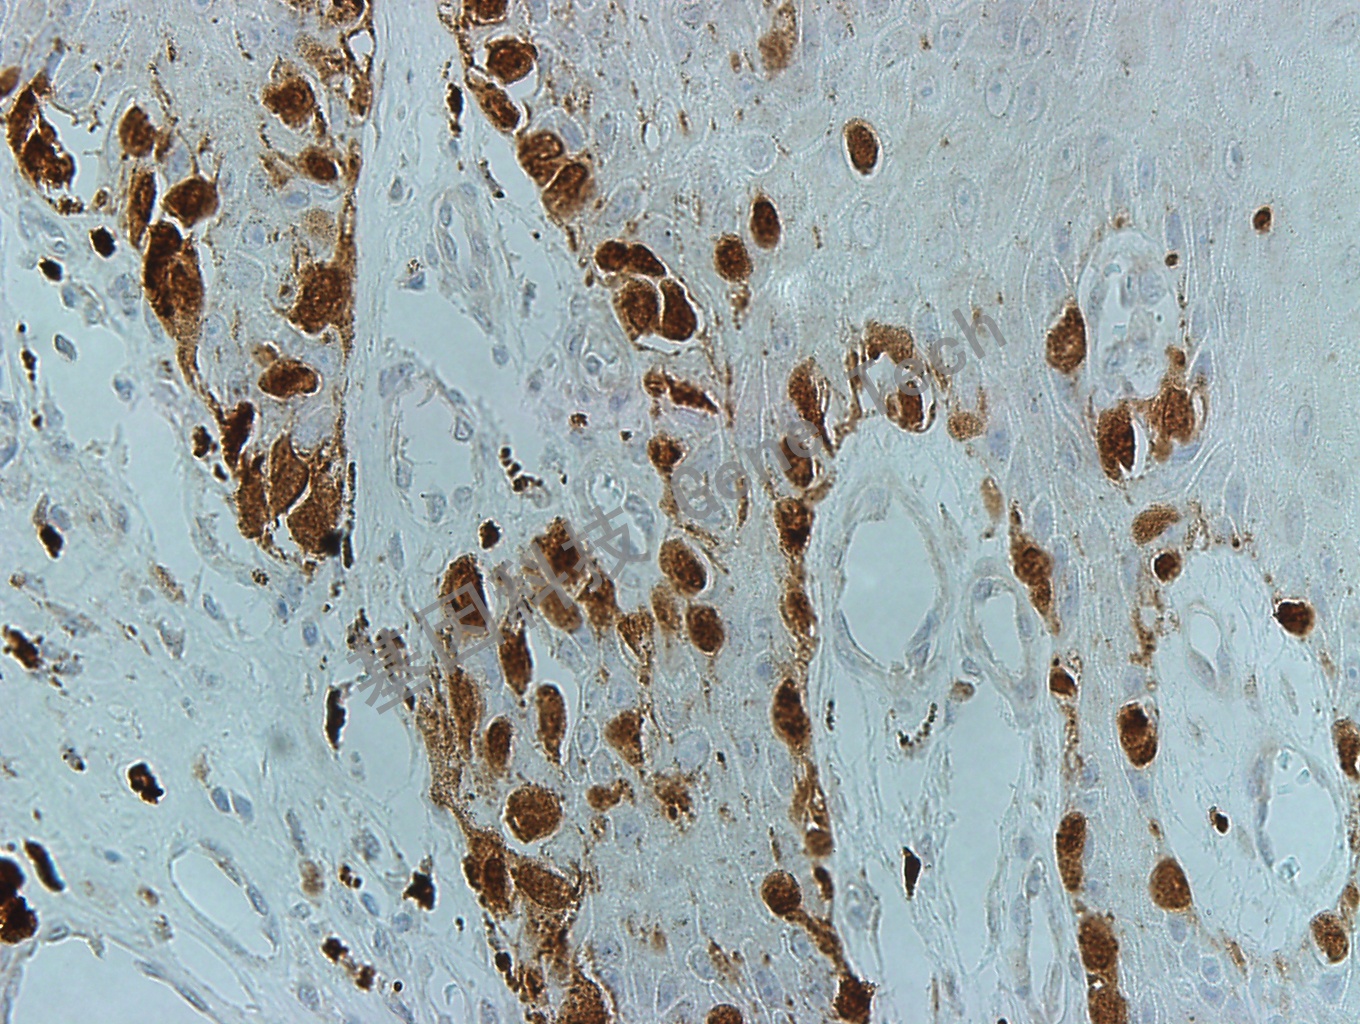

MiTF 鼠抗人 小眼相關(guān)轉(zhuǎn)錄因子(MiTF)抗體試劑(免疫組織化學法)

| 預處理:高pH熱修復 | 陽性部位:細胞核 | 陽性對照:黑色素瘤 |

| 簡介:MiTF(Microphthalmia-associated transcription factor, 小眼畸形相關(guān)轉(zhuǎn)錄因子)是重要的轉(zhuǎn)錄因子。MiTF在色素細胞的發(fā)育、分化和功能調(diào)節(jié)中發(fā)揮關(guān)鍵性作用,不僅是黑色素細胞生長、分化及色素生成的主要調(diào)節(jié)蛋白,對黑色素細胞的惡性轉(zhuǎn)化以及黑素瘤的發(fā)生、發(fā)展及轉(zhuǎn)移亦發(fā)揮重要的作用。MiTF也與肥大細胞和骨骼發(fā)育密切相關(guān)。MiTF除表達于黑色素細胞及腫瘤,在巨噬細胞、破骨細胞和多種腫瘤也可能陽性。主要用于惡性黑色素瘤的診斷。 | ||

| 黑色素瘤石蠟切片,用 MiTF(GT2263)染色,細胞核陽性,DAB 顯色。 | ||